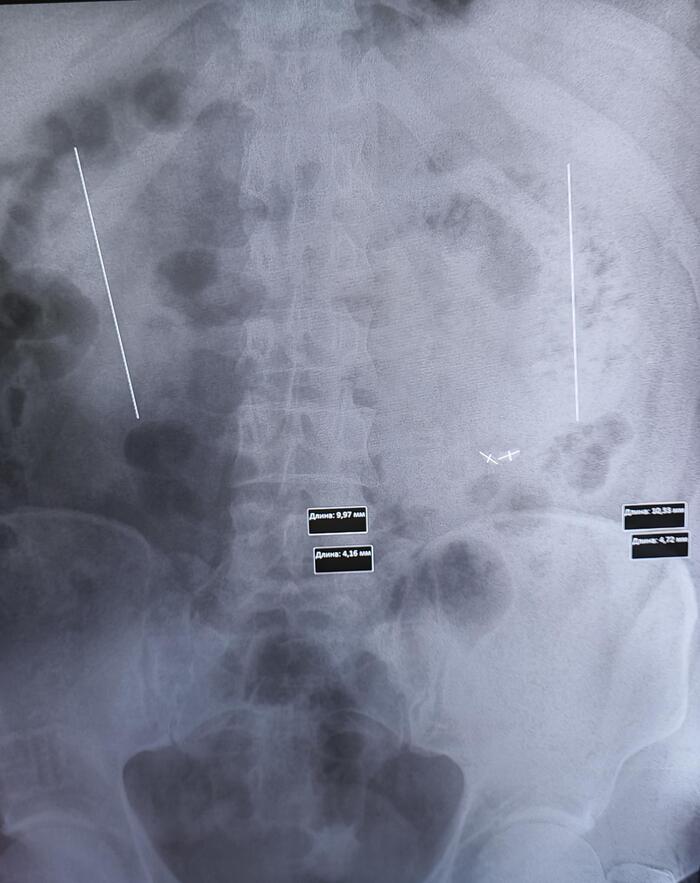

Описание: Правая почка размерами 52х53х140 мм. Корковое и мозговое вещество дифференцируются. Толщина паренхимы до 18 мм. В структуре - множественные кисты до 59*48 мм, с тонкими перегородками до 2 мм, без кальцинатов.Чашечно-лоханочная система почки не расширена, размер лоханки на выходе из почки – 4 мм. Паранефральная клетчатка не изменена.Ворота почки ориентированы в соответствии с нормой. Отхождение почечной артерии от брюшной аорты обычное.Мочеточник – не расширен – до 2 мм в диаметре.Левая почка размерами 49х52х99 мм. Корковое и мозговое вещество дифференцируются. Толщина паренхимы до 17 мм. В структуре - множественные кисты до 61*49 мм, с тонкими перегородками до 2 мм, без кальцинатов.Чашечно-лоханочная система почки не расширена, размер лоханки на выходе из почки – 4 мм. Паранефральная клетчатка не изменена.

Заключение: Множественные кисты обеих почек (Bosniak I).